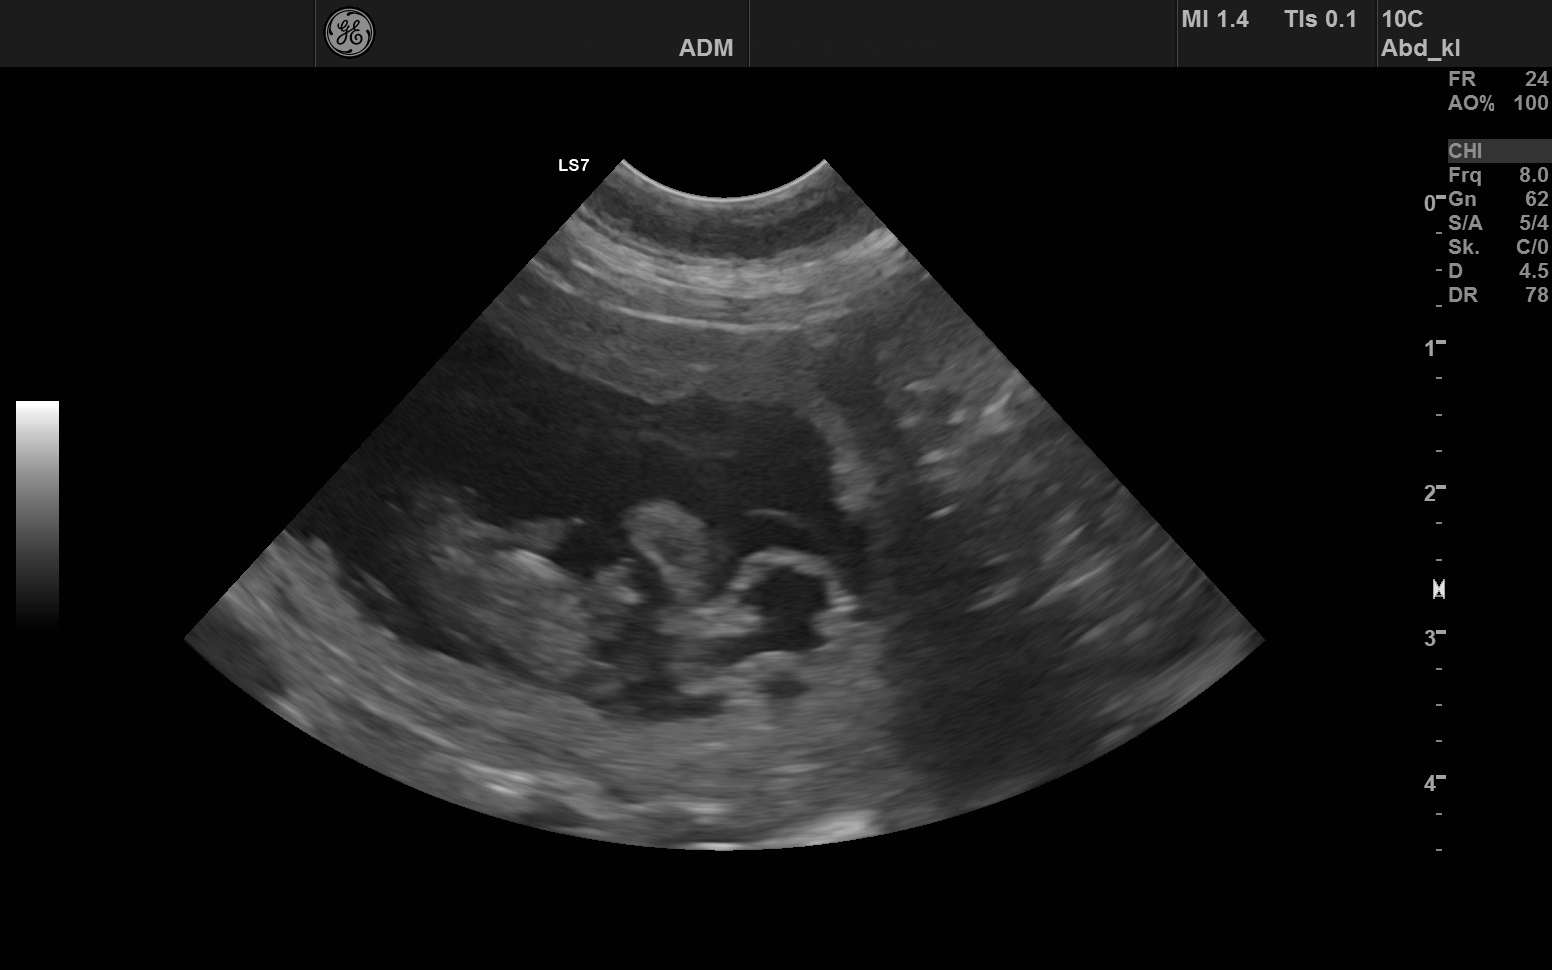

Der Ultraschall – die ersten Herzschläge

Ein ganz besonderer Moment:

Der erste Ultraschalltermin.

Als wir die kleinen Herzschläge auf dem Monitor gesehen haben,

wussten wir – bald dürfen wir neues Leben auf dieser Welt begrüßen.

Es war ein unbeschreiblich schönes Gefühl,

die ersten zarten Bewegungen unserer zukünftigen Welpen zu sehen.